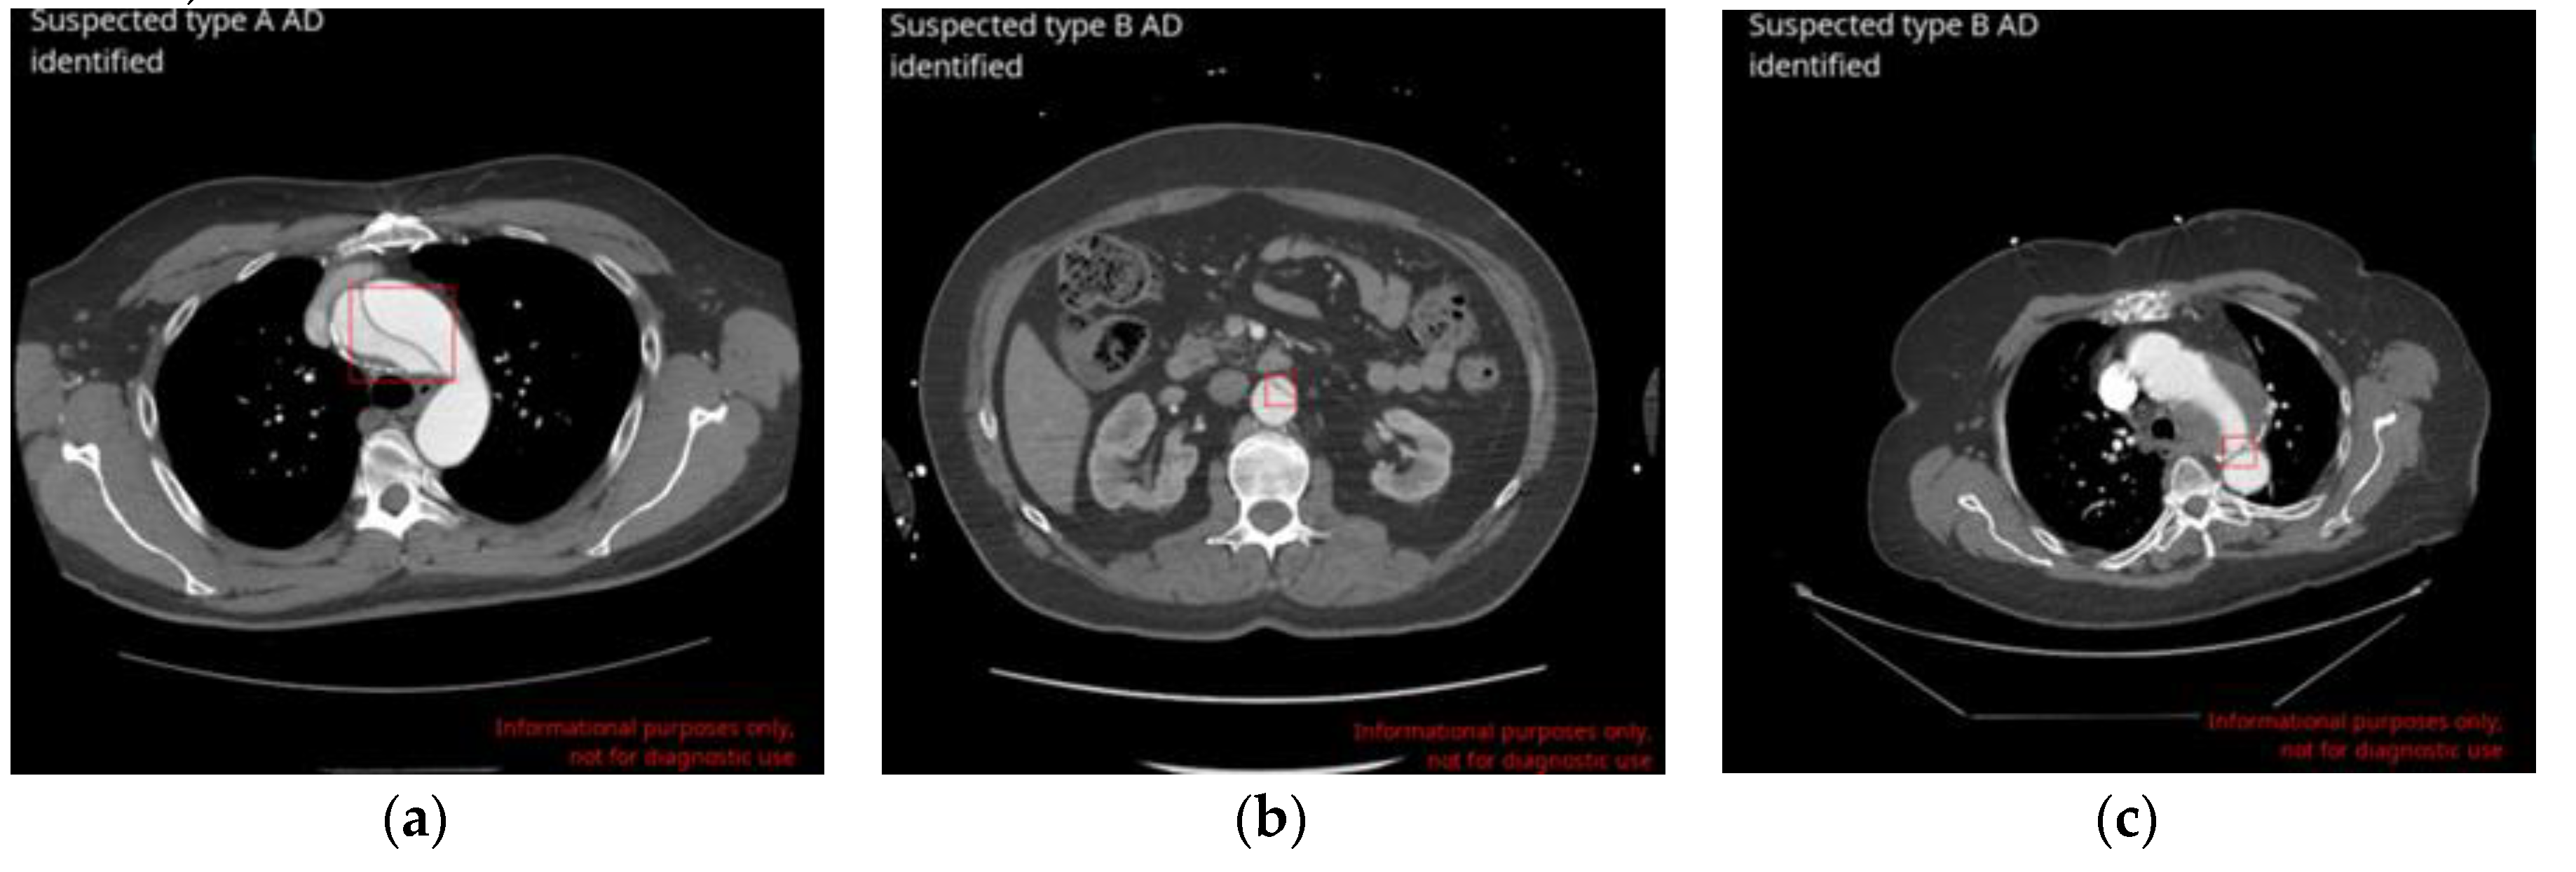

| Type A | 100 [92.8-100] | 99.4 [98.8-99.8] | 99.5 [98.9-99.8] |

| Type B | 89.2 [79.3-94.9] | 97.9 [97.0-98.7] | 97.5 [96.4-98.3] |